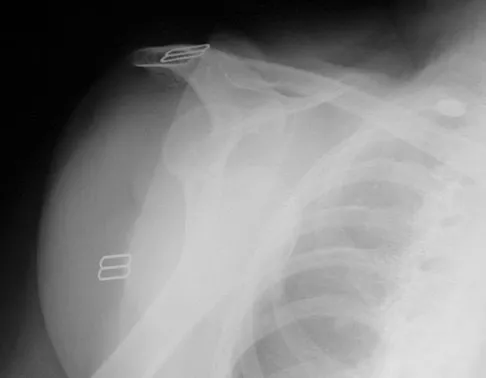

A paraplegic 32-year-old man was pulling himself up in bed by grasping the headboard rails when he felt a pop and immediate pain. A radiograph and CT scan are shown in Figures 2a and 2b. Based on these findings, management should consist of

The coracoid process is an essential component of the superior shoulder suspensory complex and must be maintained. Open reduction and internal fixation is recommended if the fragment is large and displaced more than 1 cm. Froimson AI: Fracture of the coracoid process of the scapula. J Bone Joint Surg Am 1978;60:710-711.